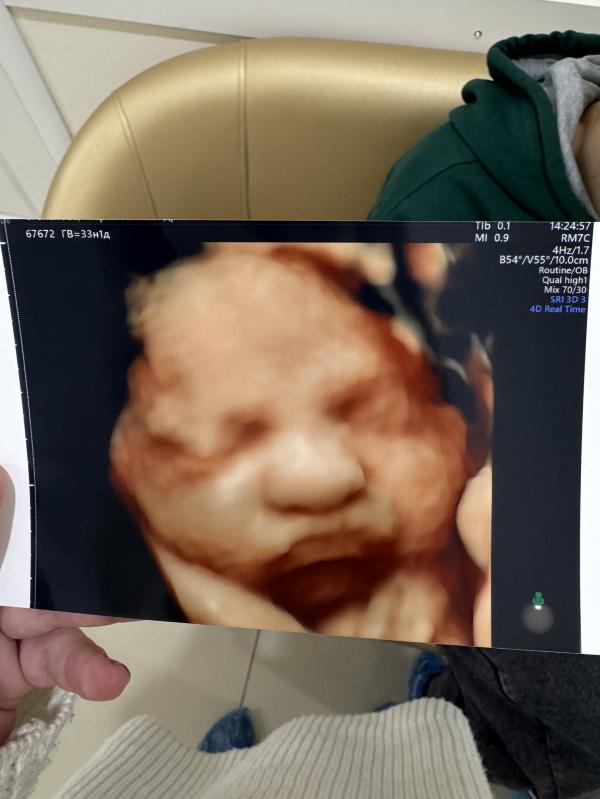

Моя маленькая булочка🥹

До этого видела ее на узи 6 января, все гадала как она там, как лежит, как растет, как живет)

Недовольно надутые губки, пришлось же развернуться для фотосессии, а то так двигали, тыкали этим датчиком)

Интересный момент с шевелениями, голова внизу, но и шевеления я чувствую в основном внизу и в боку, в ребра не прилетает, хотя казалось бы, голова то внизу 😄

Ну красотка 🦋